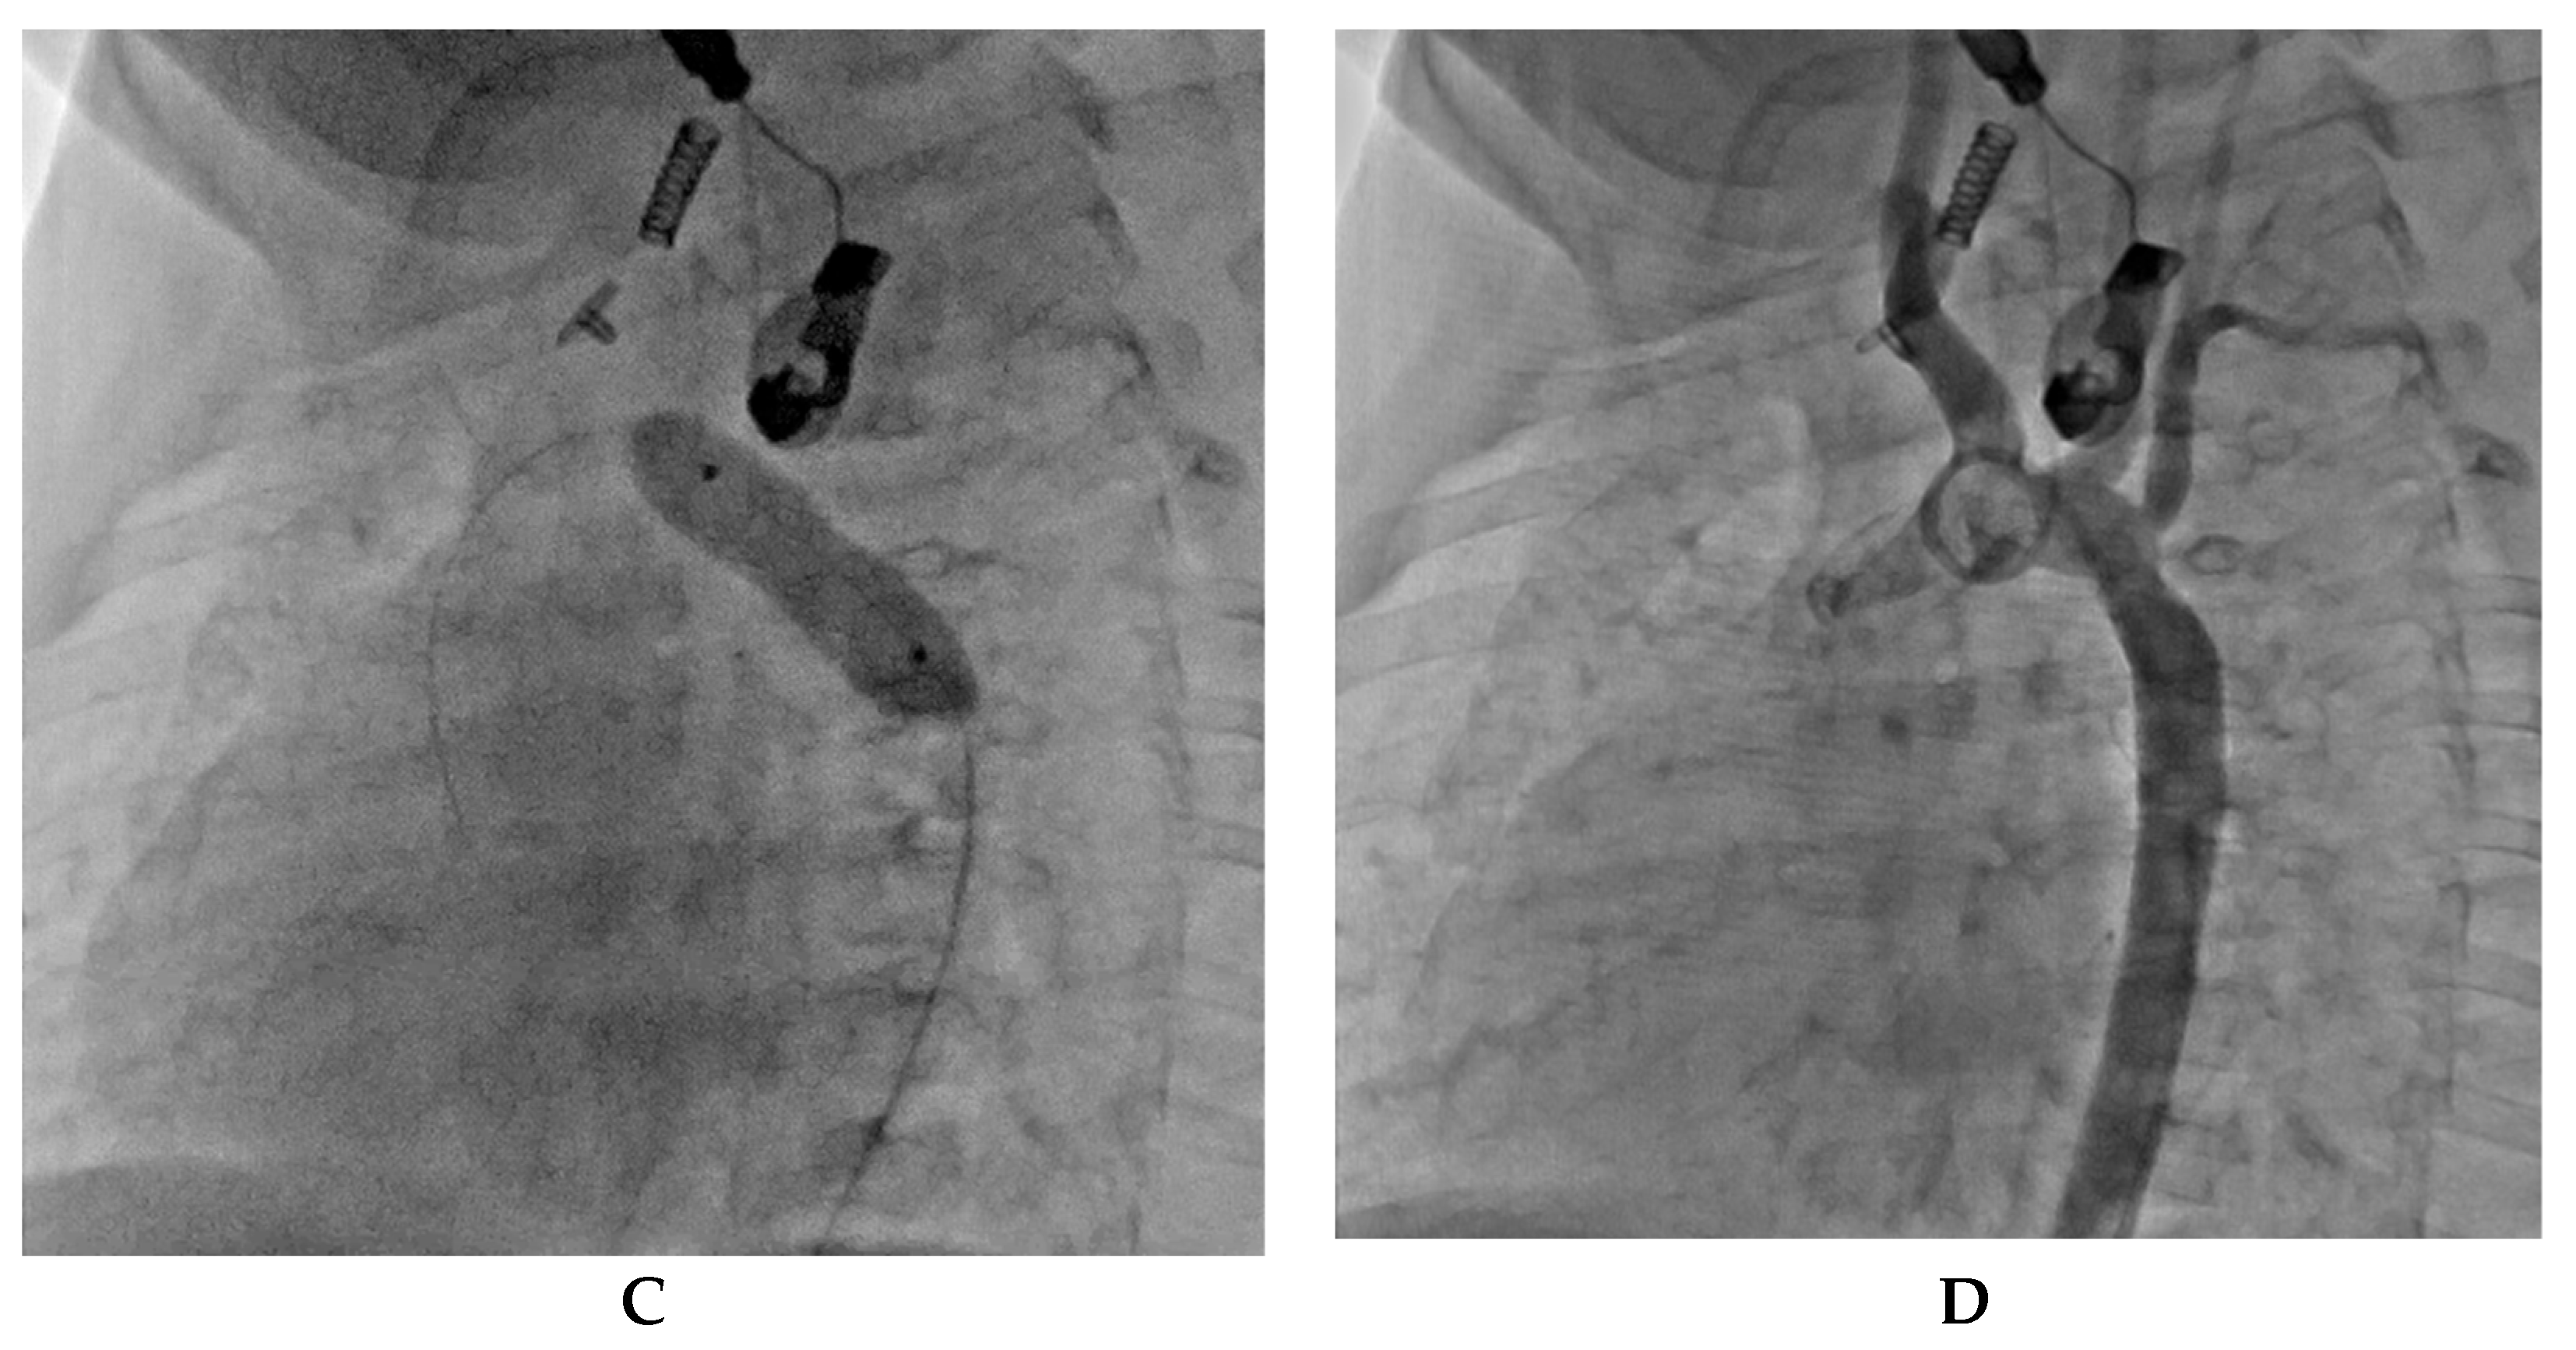

7. Our Experience-Case Series